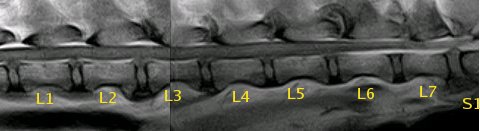

Resonancia magnética (SE T1 sagital) de la columna lumbar |